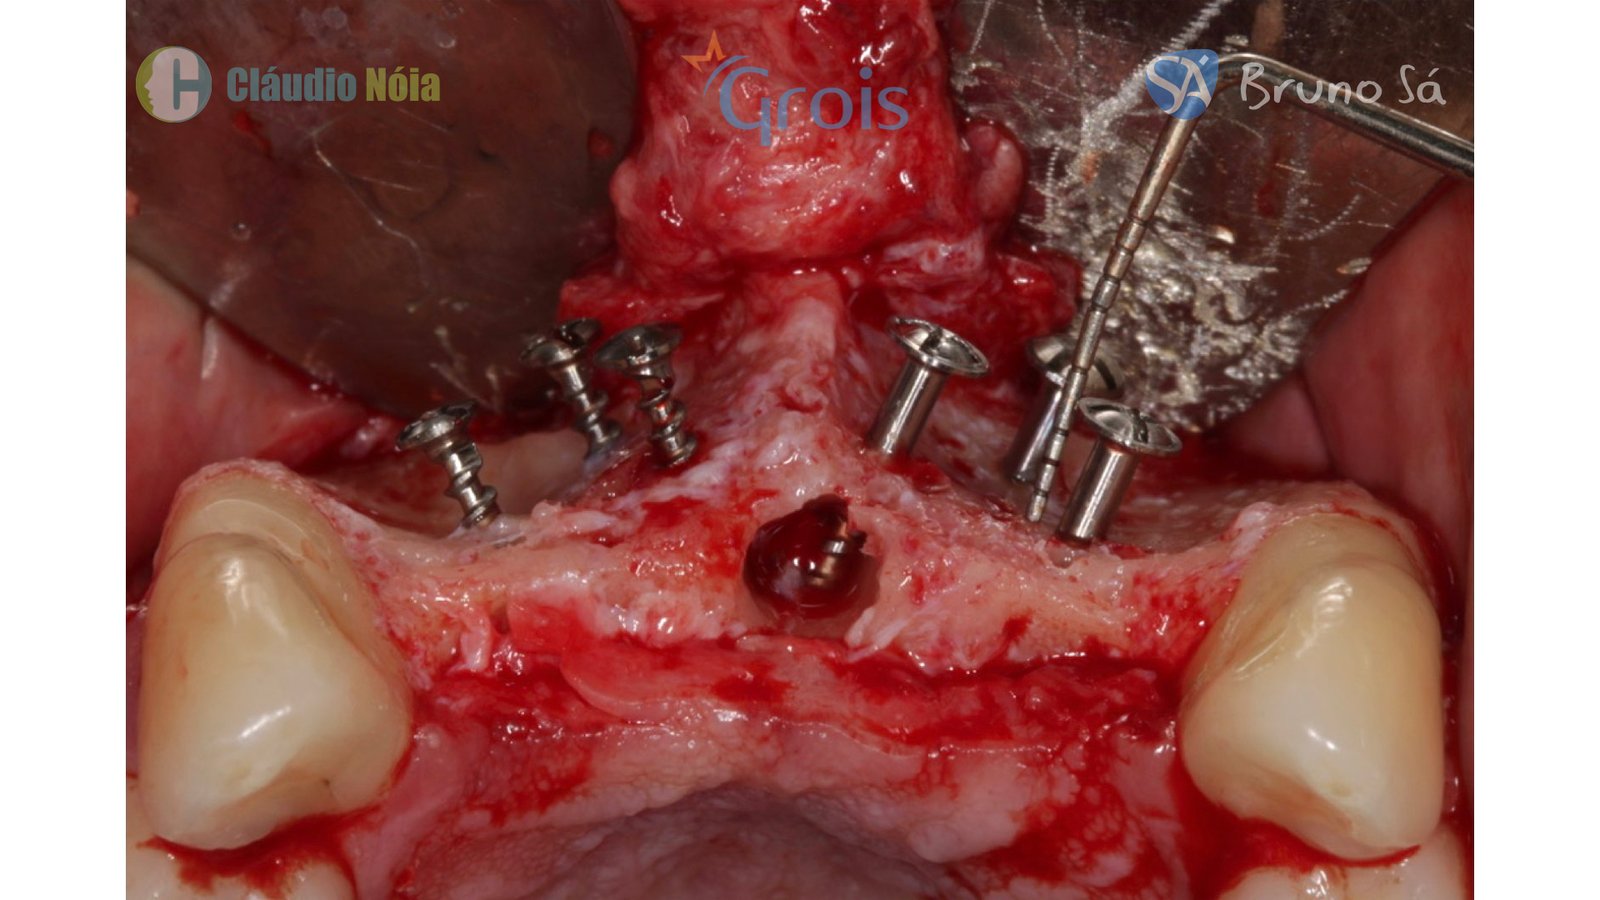

Paciente apresentou-se a Área de CBMF da Instituição com a pré-maxila edêntula (Figuras 1, 2 e 3) e foi submetido a técnica Screw Tent Pole utilizando os parafusos da linha Orth – Implacil de Bortolli (Figura 3). Do lado direito da pré-maxila foram instalados 3 parafusos que apresentavam roscas em toda superfície, enquanto que do lado esquerdo foram instalados 3 parafusos que não apresentam roscas no terço cervical (Figuras 4, 5, 6, 7 e 8). Biomaterial associado com PRF (Stick Bone) foi adequadamente acomodado na região e recoberto por membranas de PRF (Figuras 9, 10 e 11). Uma sutura livre de tensão foi realizada para finalizar o procedimento cirúrgico (Figuras 12 e 13).